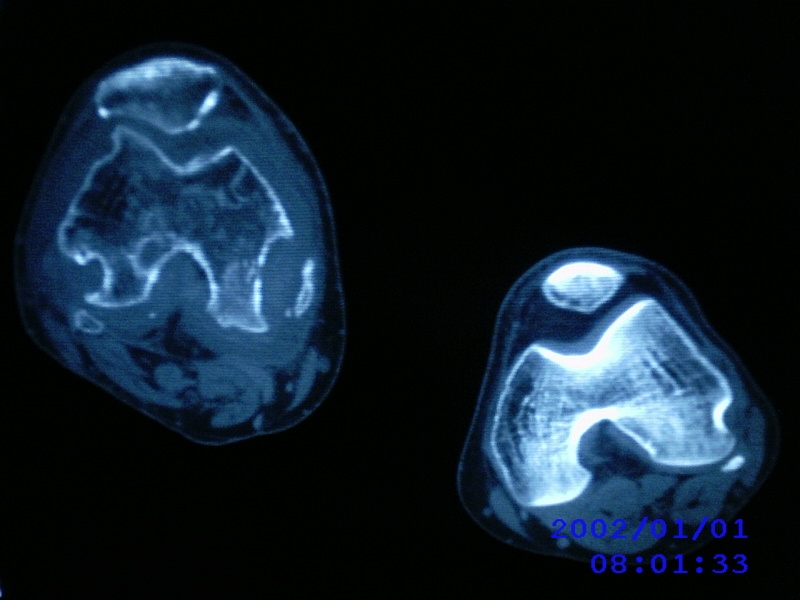

患者,男性,57岁,右侧膝关节疼痛伴肿脹10余年,加重一个月。

关节积液,关节间隙变窄,边缘骨破坏。考虑膝关节tb

关节积液,关节间隙变窄,骨质疏松,多发骨破坏,边缘轻度硬化,近端胫腓骨髓腔软组织充填,患者病史较长,支持考虑结核

有皮质的破坏~有死骨存在

结合临床表现,考虑结核。。。。课医照个胸片

支持右膝关节结核,病人如果有糖尿病、血友病等病史,还有考虑一下。

多发骨破坏,骨质疏松,关节积液。考虑右膝关节结核。